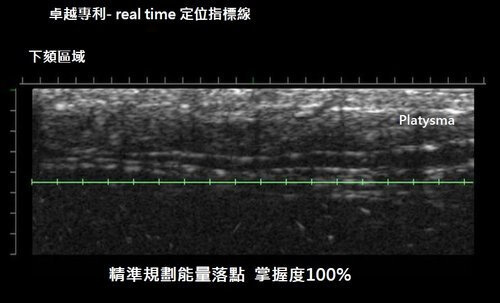

2. 即時顯像,I See You! – 極線音波拉提Ulthera是第一台在治療探頭上附設超音波顯像儀的治療機器,提供了我們專業皮膚科醫師很好的工具。

在治療中,同時可觀察到我們治療的目標- 筋膜層,並且可以避開不需要打到的重要血管神經或是骨骼系統,大大的提高了治療的安全性。

我們還可以透過這顯像系統來觀察皮膚的厚薄與退化程度,作為調整與分配治療能量的參考(下圖擷取自Ulthera網站)